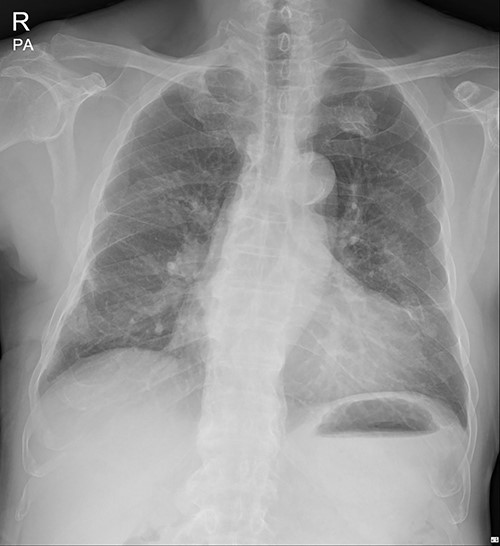

The submuscular emphysema, however, was increased in size, and the patient was eventually re-hospitalized. A small incision was made beneath the surgical wound under local anesthesia, and a 10 FR thoracic drainage catheter was carefully placed into the submuscular layer (Fig. 4.). Under 2 L of oxygen supplement, the submuscular emphysema gradually decreased over several days, and the patient was finally discharged on hospital Day 6 (Fig. 5). Since his last readmission, there have not been any more complications.

Chest X-ray after applying a 10 FR drainage thoracic catheter into the submuscular layer (11 March 2022).